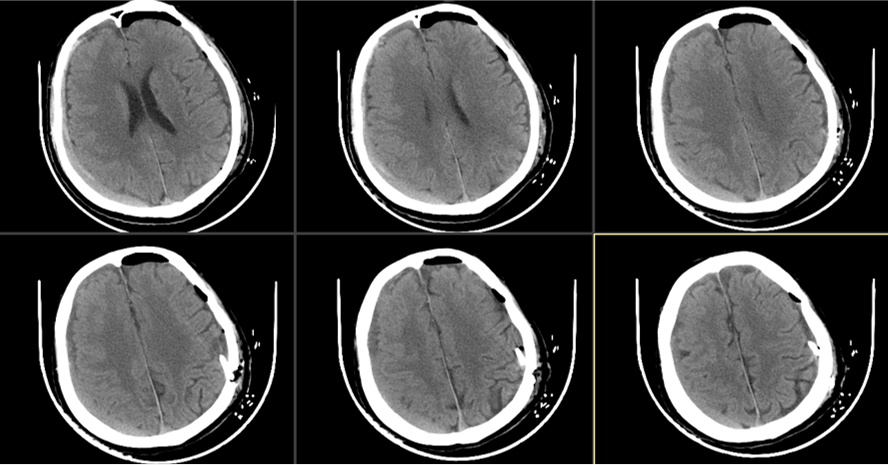

患者约2个月前无明显诱因(否认外伤史)间断出现头痛,头痛为胀痛,左侧较明显,恶心未吐,食欲、睡眠尚可,未予特殊诊治,1个月前患者头痛逐渐加重,思睡,反应略迟钝,行头部CT检查示“慢性硬膜下血肿(双侧)”,于2018年12月15日行颅骨钻孔引流术(左)。术后9天患者恢复良好出院。出院后2周于2019年1月9日患者头痛再次加重,伴有反应迟钝,走路困难,疲乏无力再次就诊,头部CT示“慢性硬膜下血肿(右侧)”,当日再次行颅骨钻孔引流术(右)。术后患者一般状态逐渐好转,无抽搐,无尿便失禁。

2019年1月9日第二次入院

近3天头痛明显,生活严重受限。有过尿失禁。查:神志清,反应迟钝,走路不稳,血压160/95mmHg,颈软,左侧肌力III级。

2019年1月13日

间断头痛明显,生活基本自理。查:神清语明,血压150/90mmHg,颈软,左侧肌力V-级。

2019年1月16日

术后当日(2019年1月16日)

术后3天(2019年1月18日)